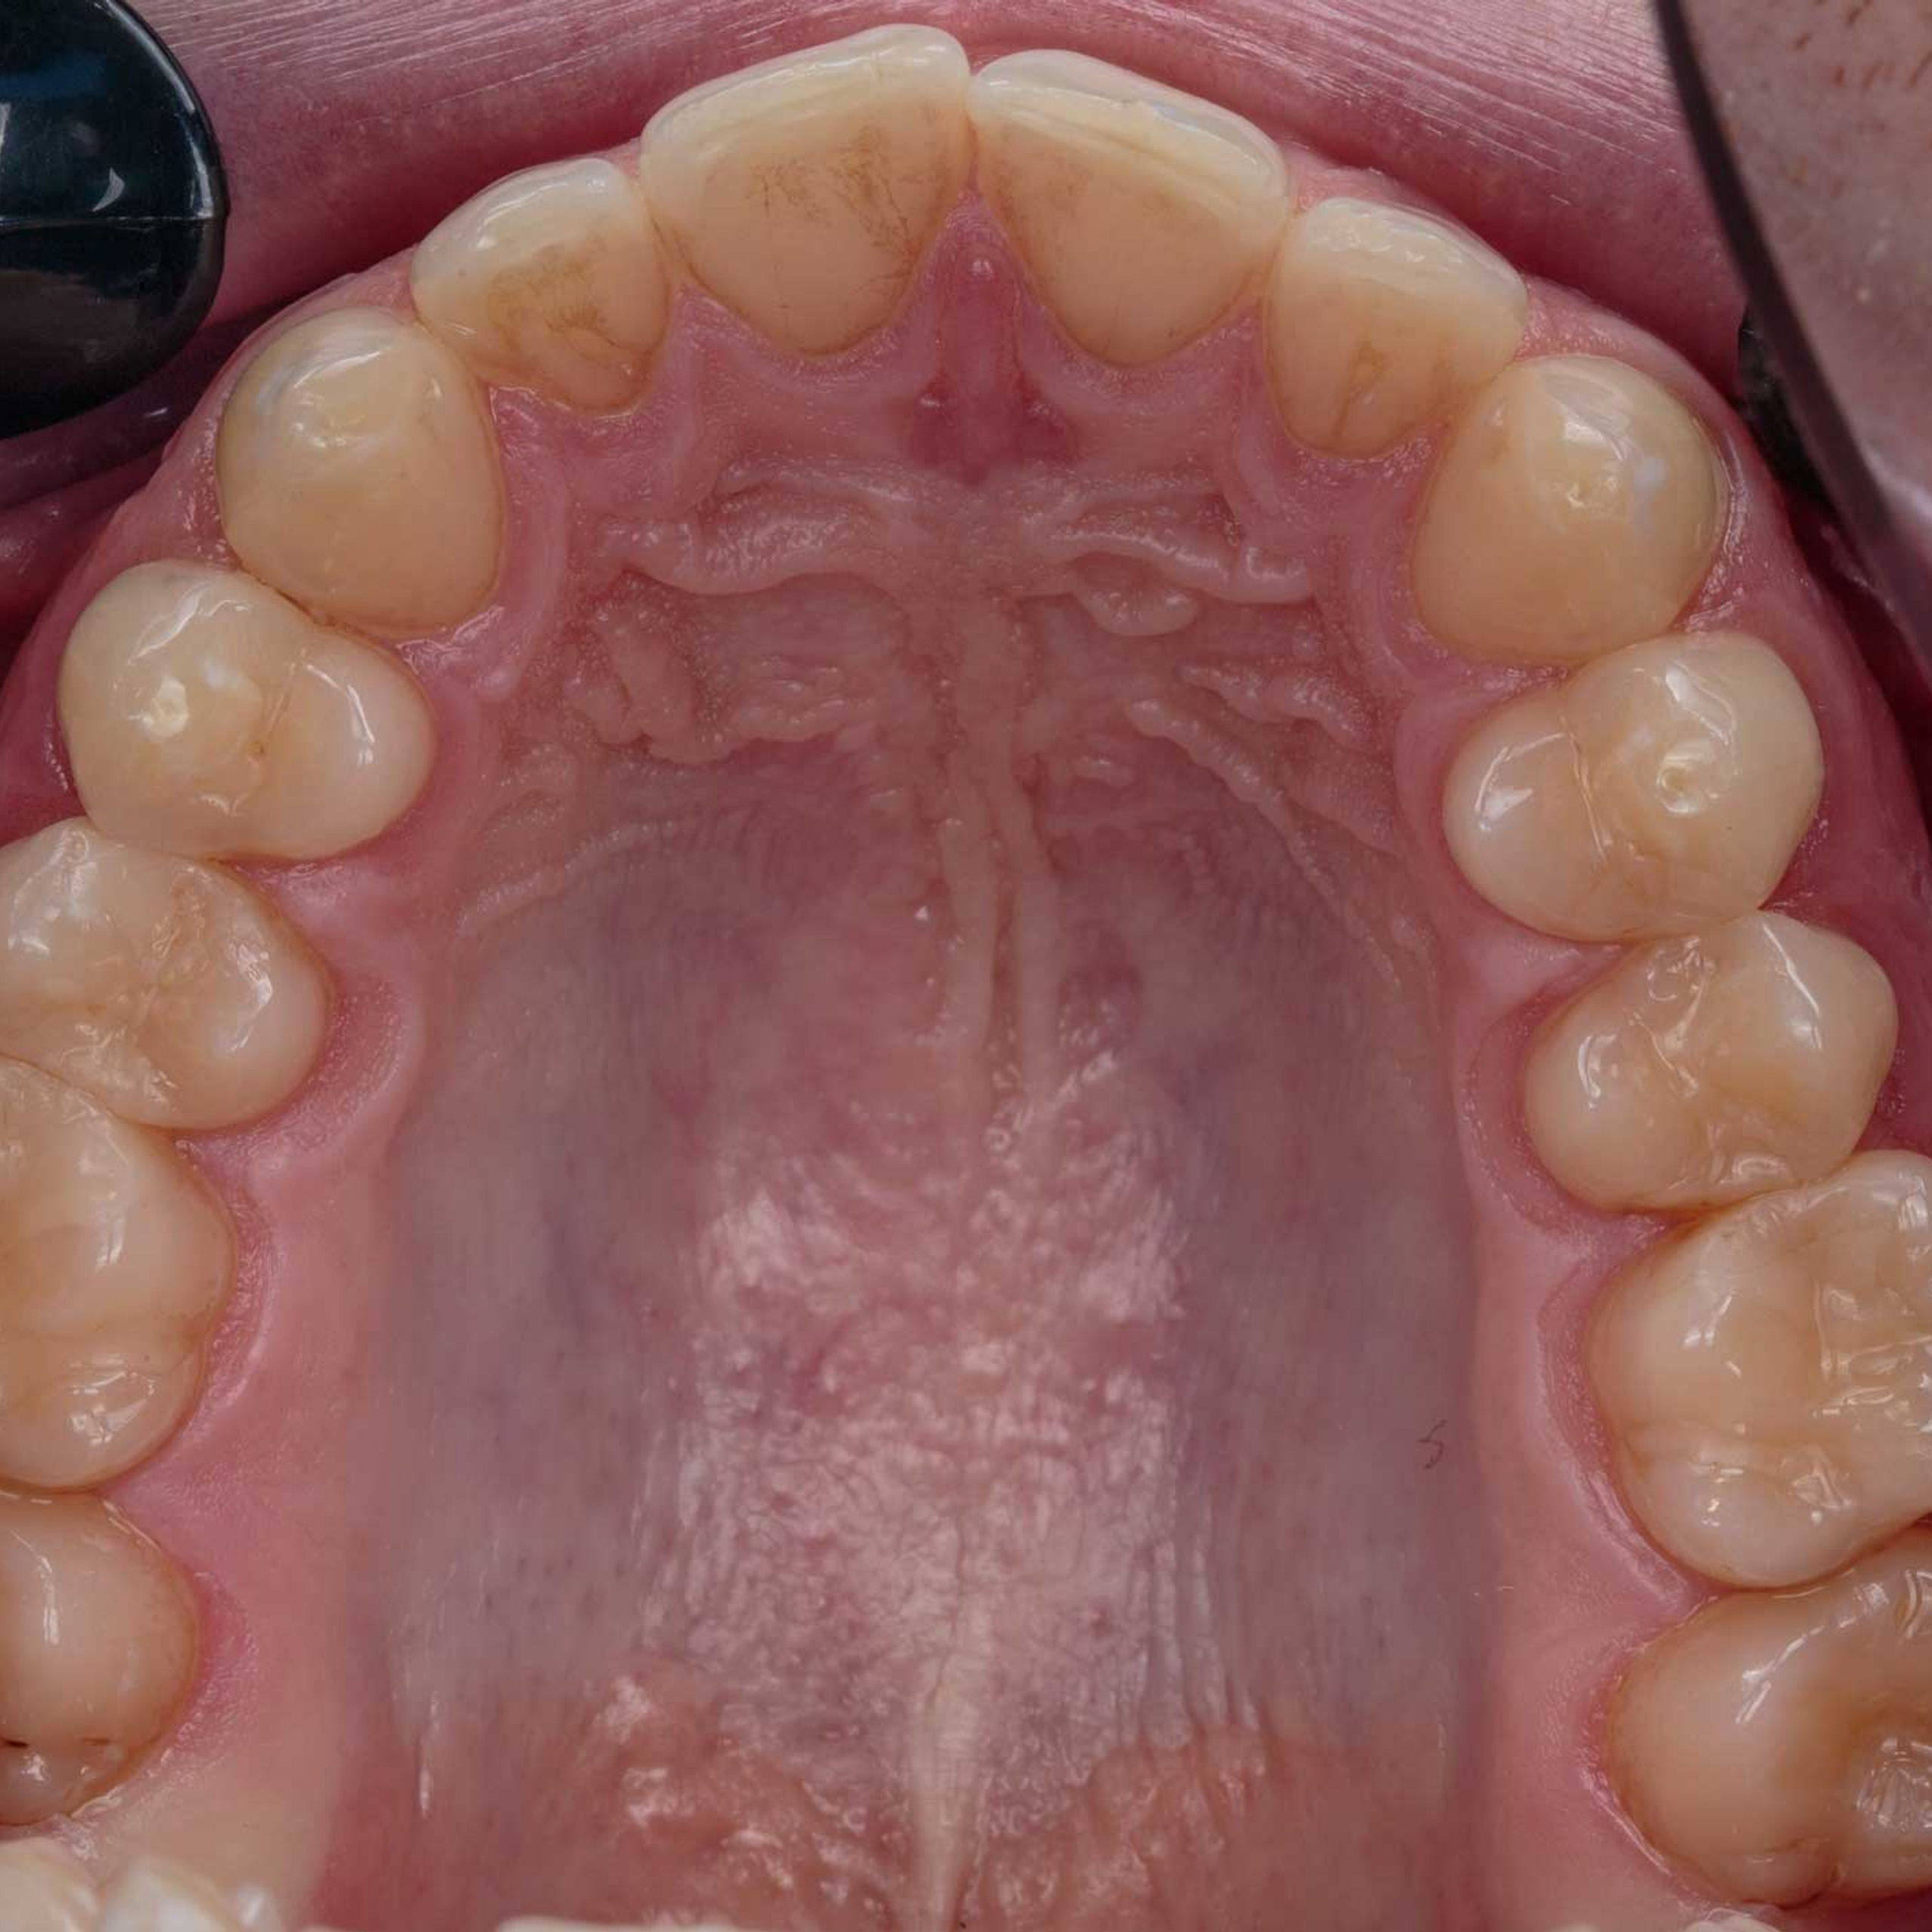

Фотографии учеников до обучения

Фотографии после обучения